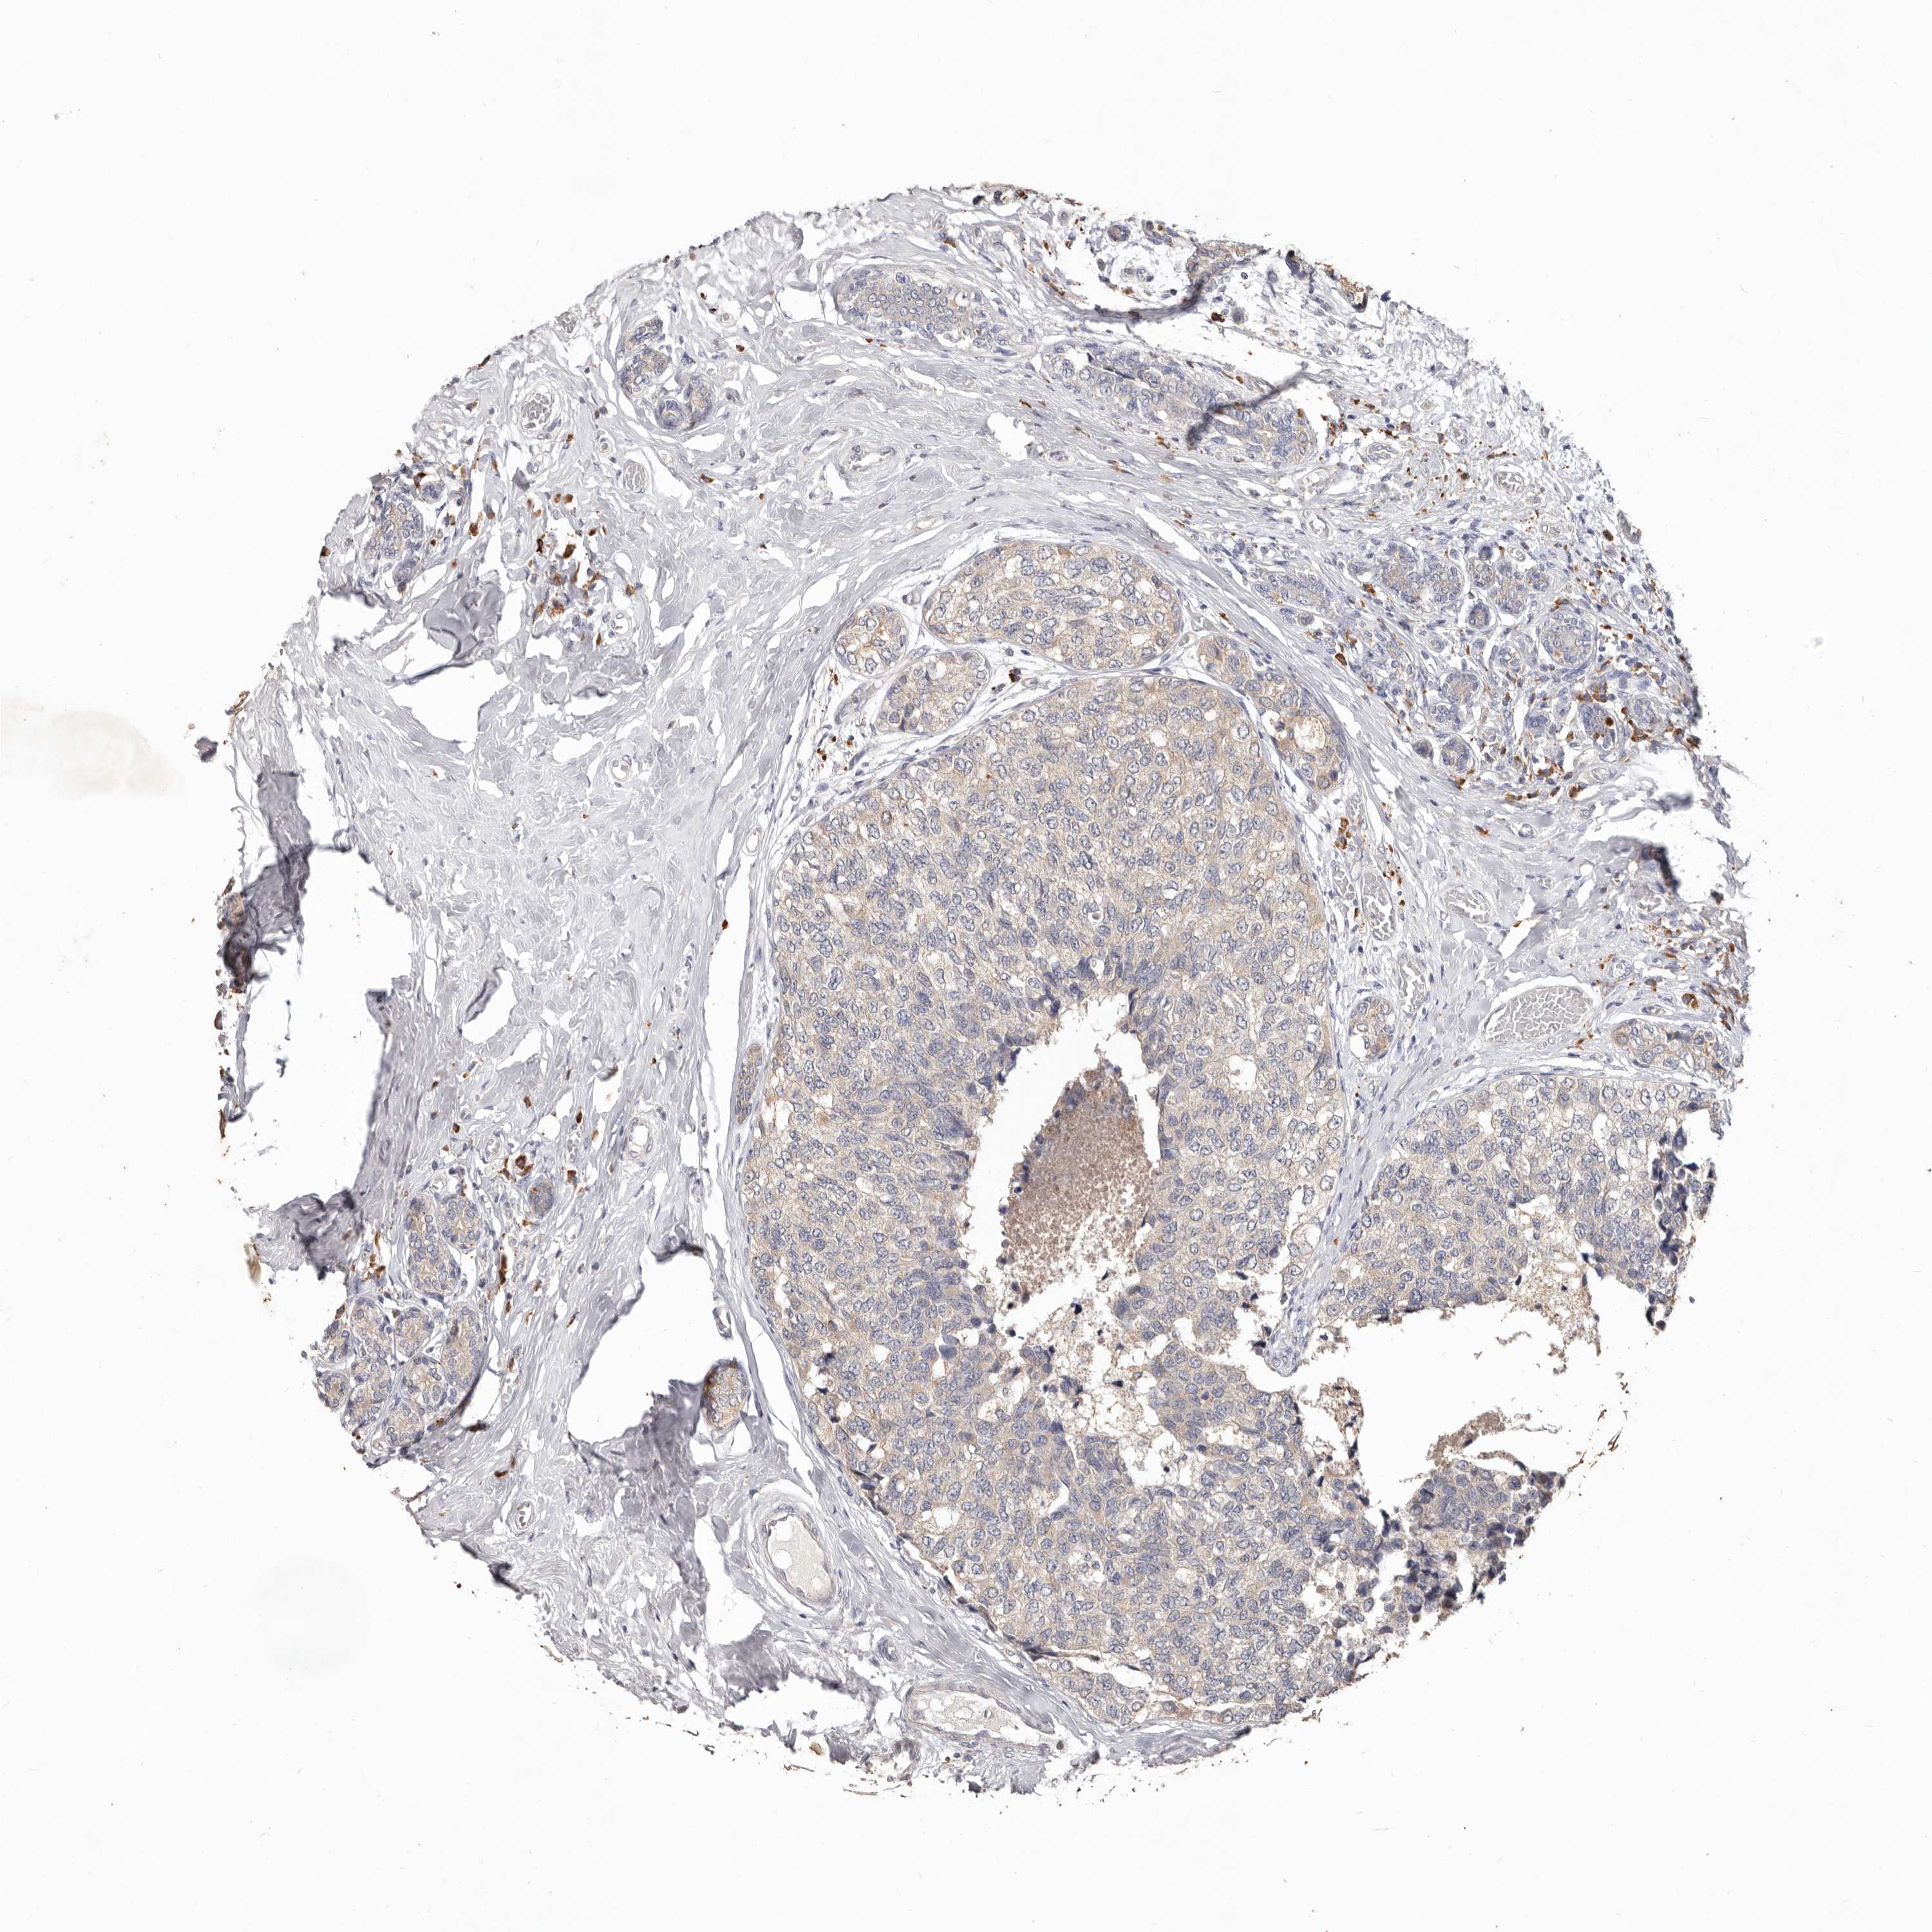

CANCER BREAST CANCER Show tissue menu

BRCA TCGA BRCA VALIDATION PROTEIN EXPRESSION